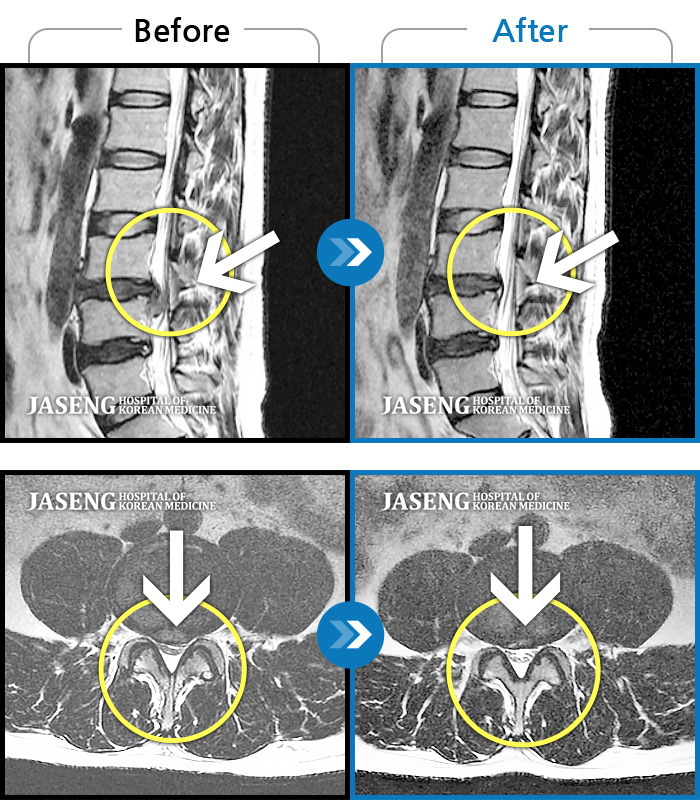

MRI 치료사례

허리 골반 통증, 앉을 때 우측 다리 당김 및 저린 증상